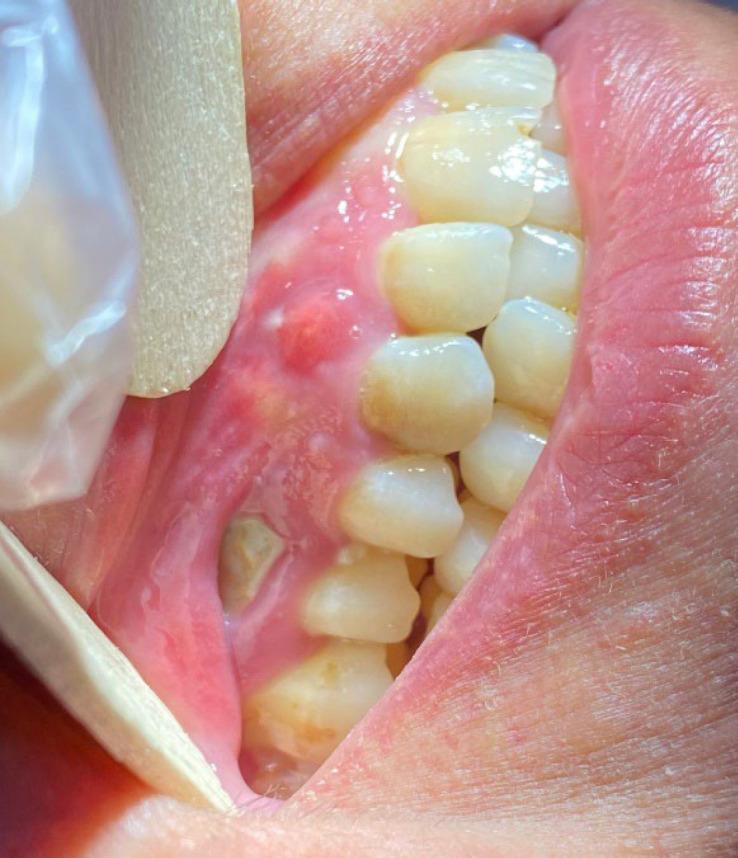

Two Cases of COVID-Related Osteonecrosis of the Jaws: A New and Worrying Entity Is Emerging.

Many people were affected by COVID-19 in its severe form. Some intercurrences are still emerging. We here report two cases of COVID-related osteonecrosis of the jaws (CRONJ). Two retrospective cases were admitted into Imam Reza Hospital, Mashhad, Iran with suspected CRONJ. One patient escaped from hospital while the other showed a positive result after our proposed treatment. A new aftermath to COVID-19 infections is emerging. Maxillofacial and orthopedic surgeons should be aware of this situation. CRONJ should be on the suspect list in patients with COVID-19. Measures that are useful in the treatment carried out, as well as some measures recommended in the literature, were discussed. Surgical treatment of CRONJ appears to be an effective alternative, especially in the more aggressive cases.